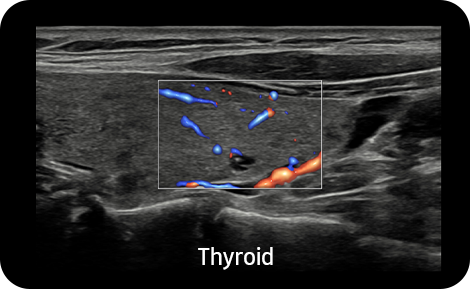

S-Flow™, směrová technologie Power Doppler, pomáhá detekovat periferní cévy. Umožňuje přesnou diagnózu v případech, kdy je vyšetření krevního průtoku velmi obtížné.

Vizualizace pomalého toku v mikrovaskulárních strukturách |

MV-Flow™ nabízí pokročilé barevné zobrazení pro vizualizaci pomalého průtoku v mikrovaskulárních strukturách. Vysoká snímková frekvence a pokročilé filtrování umožňují MV-Flow™ poskytnout detailní pohled na průtok krve, ve vztahu k okolní tkáni nebo patologii, se zvýšeným prostorovým rozlišením.